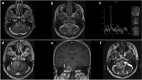

Glioblastomas presenting topographically at the cerebellopontine angle (CPA) are exceedingly rare. Given the specific anatomical considerations and their rarity, overall survival (OS) and management are not discussed in detail. The authors performed an integrative survival analysis of CPA glioblastomas. A literature search of PubMed, Scopus, and Web of Science databases was performed per PRISMA guidelines. Patient data including demographics, clinical features, neuroimaging, management, follow-up, and OS were extracted. The mean age was 39 ± 26.2 years. The mean OS was 8.9 months. Kaplan-Meier log-rank test and univariate Cox proportional-hazards model identified hydrocephalus (log-rank, p = 0.034; HR 0.34; 95% CI 0.12-0.94; p = 0.038), chemotherapy (log-rank, p < 0.005; HR 5.66; 95% CI 1.53-20.88; p = 0.009), and radiotherapy (log-rank, p < 0.0001; HR 12.01; 95% CI 3.44-41.89; p < 0.001) as factors influencing OS. Hydrocephalus (HR 3.57; 95% CI 1.07-11.1; p = 0.038) and no adjuvant radiotherapy (HR 0.12; 95% CI 0.02-0.59; p < 0.01) remained prognostic on multivariable analysis with fourfold and twofold higher risk for the time-related onset of death, respectively. This should be considered when assessing the risk-to-benefit ratio for patients undergoing surgery for CPA glioblastoma.